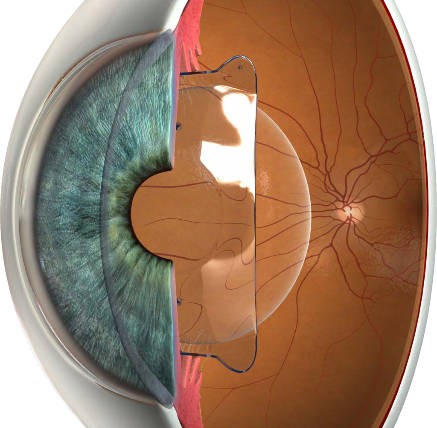

前房深度

中央区深度需大于2.8mm。

ICL晶体在眼内的状态是四角卡于睫状沟内,中心区域“悬空”既不接触虹膜也不接触自然晶状体。悬空区域即为前房,这儿深度是否充足就直接影响是否能安全放置ICL晶体。如果前房深度不够可能导致青光眼,诱发白内障等问题。

特点?

ICL晶体植入只需一个为放置ICL通过的切口大约2mm,不切削损耗角膜,对角膜厚度无要求。具有可逆性,可取出。